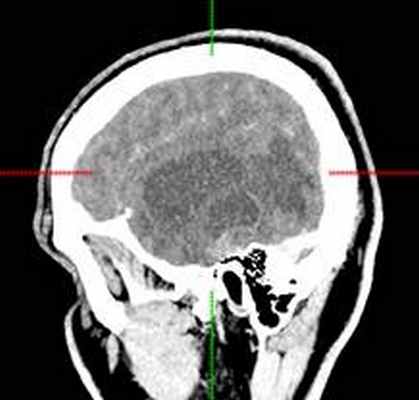

(б) МРТ, постконтрастное Т1-ВИ, аксиальный срез: у того же пациента контрастирования образования не определяется, что является типичным признаком ангиоцентрической глиомы. В смежной с опухолью области часто присутствует участок фокальной кортикальной дисплазии, который должен быть резецирован для предотвращения повторных судорожных приступов. (а) МРТ, Т1-ВИ, аксиальный срез: у шестилетнего ребенка с рефрактерной эпилепсией в структуре коры и субкортикального белого вещества определяется слабовыраженное образование. Обратите внимание на гиперинтенсивные кольцевидные участкичто типично для ангиоцентрической глиомы.

(б) МРТ, Т2-ВИ, корональный срез: у того же пациента определяется повышение интенсивности сигнала от образования, расположенного в области коры и субкортикального белого вещества правой лобной доли. При хирургической резекции была диагностирована ангиоцентрическая глиома. Визуализационные признаки могут напоминать признаки чаще встречающейся ДНЭО.